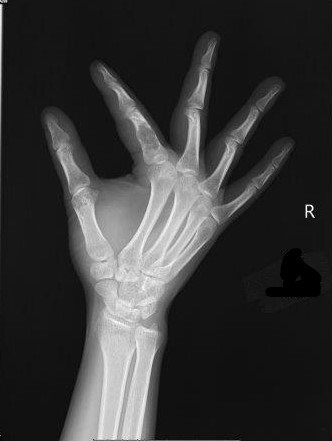

Welche Pathologie erkennen Sie am vorliegenden Röntgenbild?